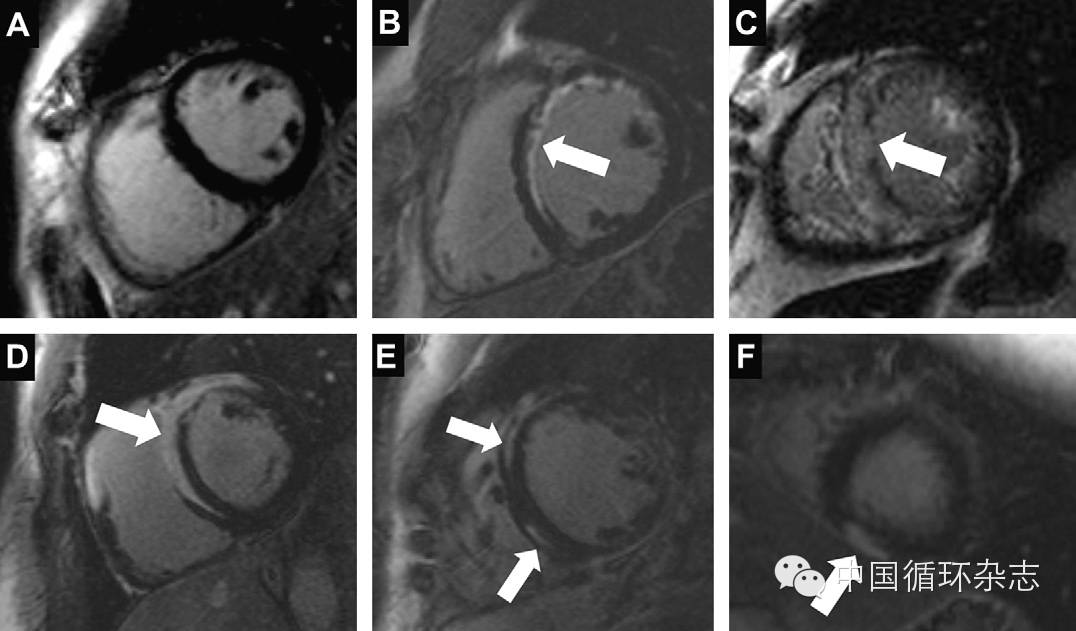

图1:

A、正常心肌组织:钆剂延迟增强没有强化

B、心梗/心肌纤维化:心内膜下延迟强化高信号

C、心肌淀粉样变性:左室增厚,心内膜下弥漫LGE强化

D、心肌结节病:左室前壁、室间隔、右室壁心外膜强化

E、扩张性心肌病:壁间延迟强化

F、活动性心肌炎:心外膜下片状延迟强化